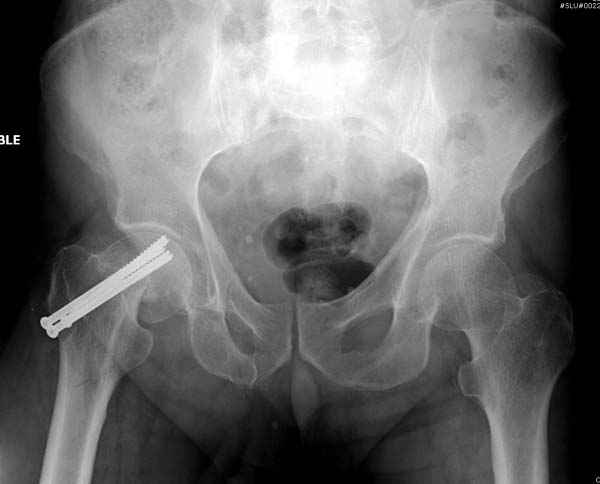

[Ortho] неполный перелом шейки

Профилактику дальнейшего раскола неполного перелома шейки провели тремя канюлированными шурупами.

На второй день после выписки упал дома. Снимки приложены. Коллеги рекомендуют удаление шурупа и вытяжение. Что делать?